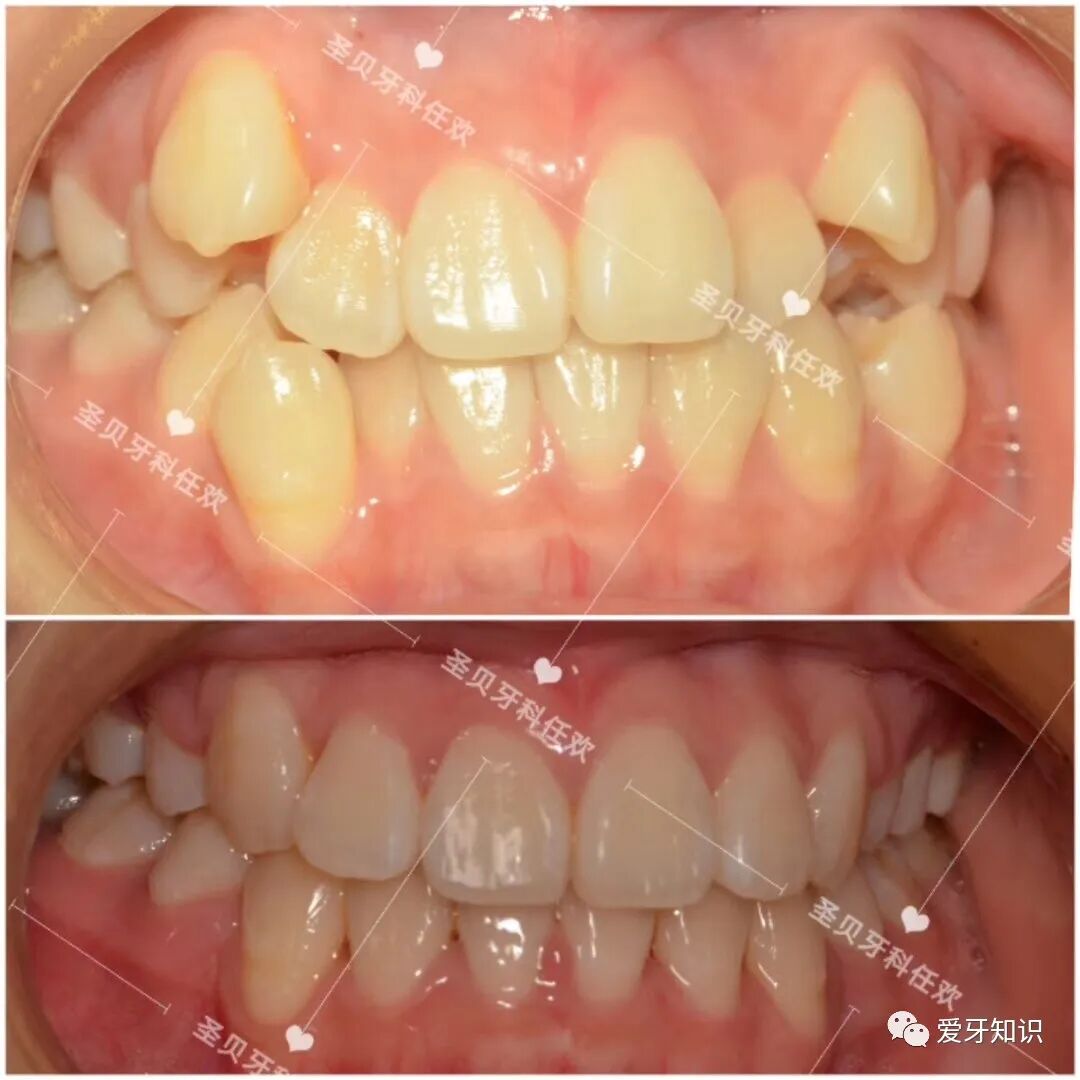

很多人觉得自己嘴太凸了不好看

高中的时候爱美意识就已经觉醒,这拿不上台面的牙齿让我好是苦恼。凭心而论,牙齿不整齐我都能接受,不笑就可,但是外凸是挡不住的。偶尔听到别人议论,心里还是会有那么亿点点不舒服。

穷学生光有想法,没有家长的经济支持是整不起牙的。这一拖就到了大学这所『整容院』,化妆技术再炉火纯青,也掩饰不了外凸的牙齿!涂再好看的口红,张嘴就露怯。

像这样的龅牙+嘴凸矫正变化就很大。于是拔掉了4颗正畸牙然后内收牵引,达到嘴型变化的过程!https://mmbiz.qpic.cn/mmbiz_png/fwaTu5a4jNI7P9JsNol5Bntcf4QDLzTxjUPJxibamWl8FlvEjBXATic1e69qaO5R2qEFh1OB2ddeaiam3YD4biaZAQ/640?wx_fmt=png

现在的我牙齿整齐了!嘴不凸了!朋友还说我鼻子变挺了!

(嘴不凸了感觉人都年轻了也漂亮了,而且矫正后皮肤也变好了)